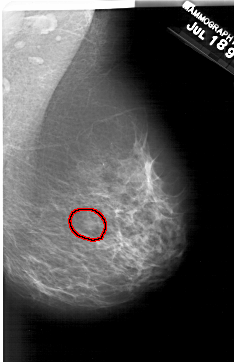

A_2001_1.RIGHT_CC

RIGHT_CC LINES 6316 PIXELS_PER_LINE 3766 BITS_PER_PIXEL 12 RESOLUTION 43.5 OVERLAY

FILE: A_2001_1.RIGHT_CC.OVERLAY

TOTAL_ABNORMALITIES 1

ABNORMALITY 1

LESION_TYPE MASS SHAPE OVAL MARGINS OBSCURED

ASSESSMENT 2

SUBTLETY 3

PATHOLOGY BENIGN

TOTAL_OUTLINES 1

BOUNDARY